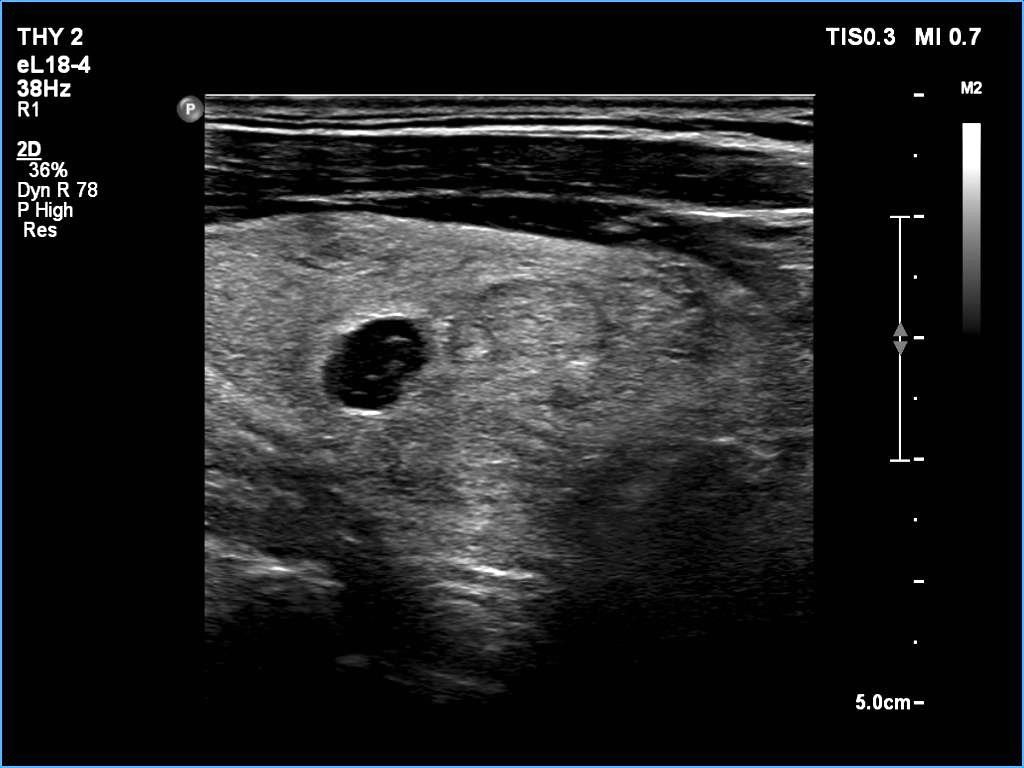

Ultrasonography: The thyroid was echonormal. There was a larger nodular mass in the right lobe which was composed of a dominantly solid echonormal portion that surrounded a dominantly cystic area. There were multiple nodules in the left lobe. The latter included an almost completely cystic lesion.

Comment. The right nodule is dominantly solid one because the cystic portion is less than 50%. The cystic portion of the nodule is multichambered which presents spongiform areas. The left cystic nodule is an almost completely cystic lesion, that has disappeared after the removal of cystic fluid.